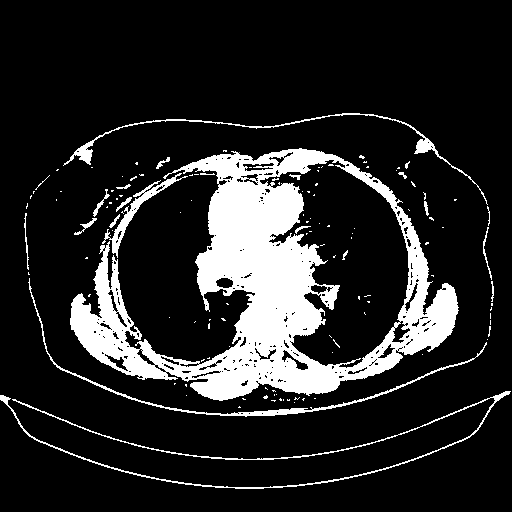

Original NATIVE CT scan (input)

Full window (WL 1023.5, WW 4095 β†’ Low βˆ’1024, High +3071)

Actual HU range: [-1024.0, 3071.0]